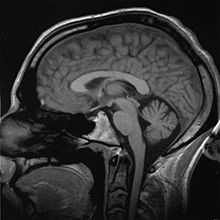

Brain

"It is well established that men have a larger cerebrum than women by about 8–10% (Filipek et al., 1994; Nopoulos et al., 2000; Passe et al., 1997a,b; Rabinowicz et al., 1999; Witelson et al., 1995)." However, what is functionally relevant are differences in composition and "wiring". Richard J. Haier and colleagues at the universities of New Mexico and California (Irvine) found, using brain mapping, that men have more grey matter related to general intelligence than women, and women have more white matter related to intelligence than men – the ratio between grey and white matter is 4% higher for men than women.

Gray matter is used for information processing, while white matter consists of the connections between processing centers. Other differences are measurable but less pronounced. Most of these differences are produced by hormonal activity, ultimately derived from the Y chromosome and sexual differentiation. However, differences that arise directly from gene activity have also been observed.